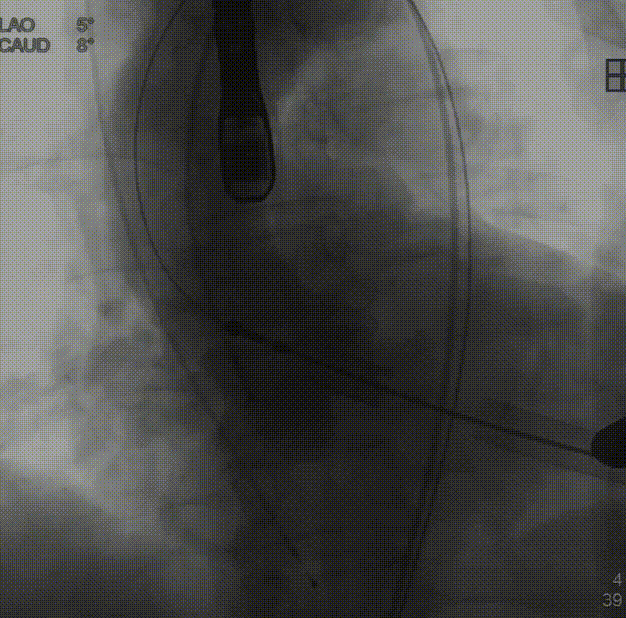

术中建议造影角度LAO 4°,CAU 6°(其它考角度如下图):

横位心,心室角度68°:

降瓣至窦部:

完成瓣膜释放:

复查根部造影,未见明显反流: